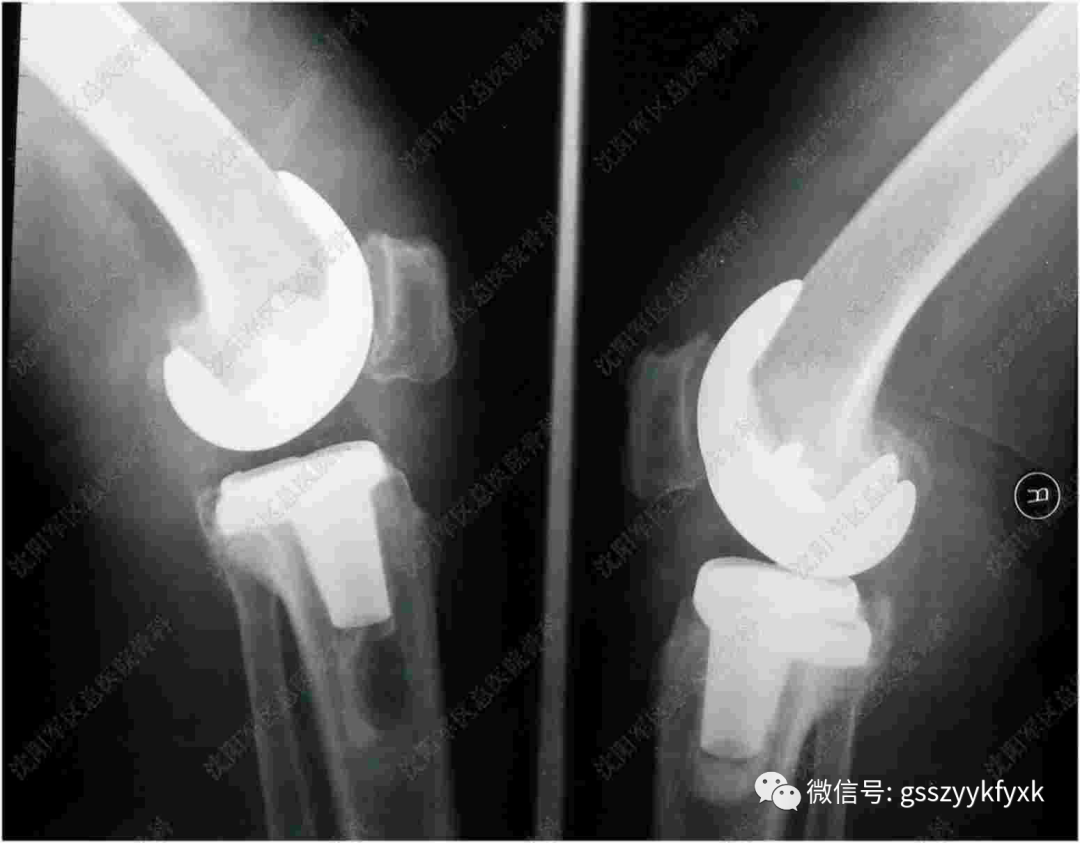

关节置换术是指用人工关节替代和置换病损关节。目前它已应用于治疗肩关节、肘关节、腕关节、指间关节 、髋关节、膝关节及踝关节等疾患,但以全人工髋关节及膝关节置换最为普遍。

人工髋关节手术适应症